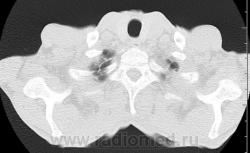

На фоне консолидации полость без содержимого. Может быть всё что угодно, что сопровождается деструкцией. Нужны ещё томограммы в лёгочном окне.

Изображения выставлены все. Ваше мнение уважаемые коллеги?

Туберкулёз.

Туберкулёз?

Это КТ 2-летней давности и попало оно мне в руки, после недавнего прохождения контроля пациентом, когда мы стали перед вопросом о специфическом / не специфическом процессе.

Тогда, пациента 2 месяца лечили от пневмонии, лечили интенсивности, стационарно, в серьёзном учреждении.

Предположу аспергиллез